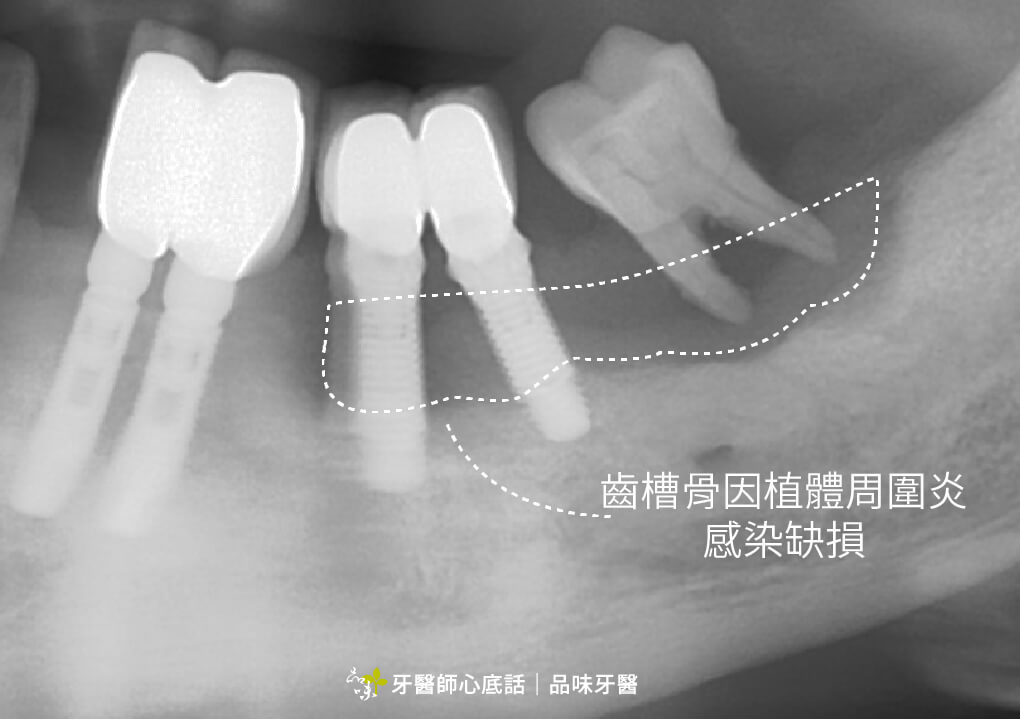

植體周圍炎

如果沒有在牙周病控制好的狀況下植牙,植體也會因此被牙周病的細菌感染,最後產生植體周圍炎(一種植牙的牙周病),最後有可能植體發炎感染,最後得移除植體。